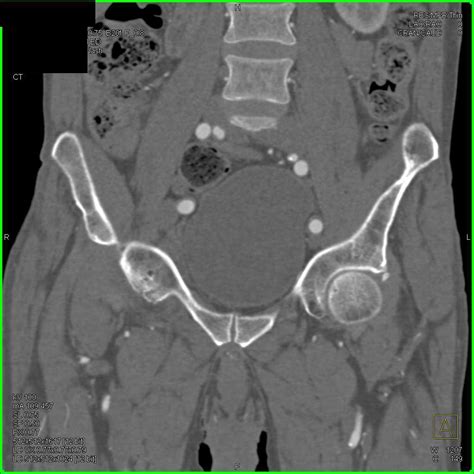

Diagnosing Hip Joint Effusion

Diagnosing hip joint effusion typically involves a combination of physical examination, medical history, and diagnostic tests. The diagnostic process may include:

• Imaging Tests: X-rays, MRI, or ultrasound to visualize the hip joint and detect fluid accumulation.

• Joint Aspiration: Removing a sample of the fluid from the hip joint for laboratory analysis.

Joint aspiration is particularly useful for identifying the cause of the effusion, such as infection or crystal deposition diseases like gout.